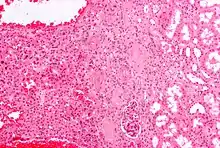

An oncocytoma is an epithelial tumor composed of oncocytes, large eosinophilic cells having small, round, benign-appearing nuclei with large nucleoli and excessive amounts of mitochondria.

Micrograph of a renal oncocytoma. H&E stain.